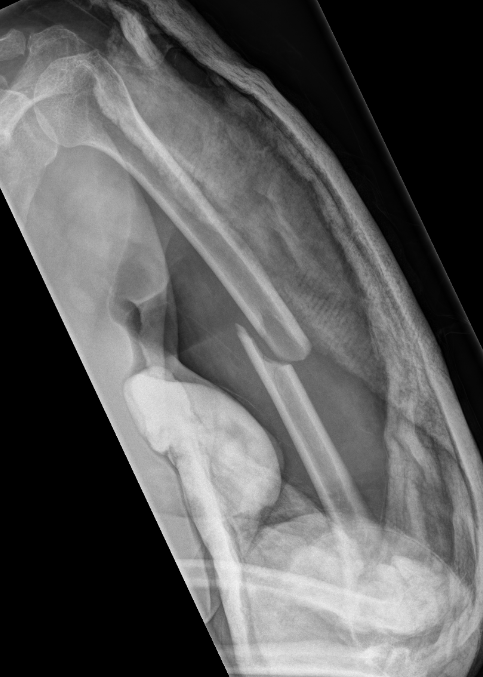

Segmental fracture ORIF

Proximal third humerus ORIF of nonunion